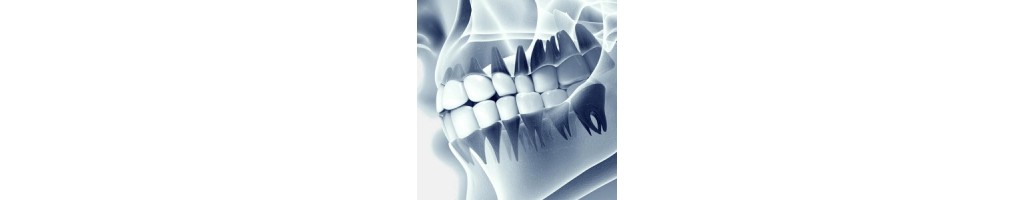

Dental görüntüleme sistemleri, diş hekimleri ve diş sağlığı profesyonelleri tarafından kullanılan çeşitli medikal görüntüleme cihazlarını içeren bir kategoriye aittir. Bu sistemler, dişlerin, çenelerin ve ağız yapısının detaylı görüntülerini elde etmek için kullanılır. Dental görüntüleme, teşhis, tedavi planlaması ve tedavi sonuçlarının değerlendirilmesi gibi birçok klinik uygulamada önemli bir rol oynar. İşte dental görüntüleme sistemleri hakkında bazı temel bilgiler:

- Panoramik Röntgen Cihazları: Bütün ağız yapısını tek bir görüntüde gösteren cihazlardır.

- Periapikal Röntgen Cihazları: Diş kökleri ve çevresindeki dokuların detaylı görüntülerini sağlar.

- Diş Tomografi (CBCT): Üç boyutlu görüntüleme sunan, özellikle implant cerrahisi ve diğer kompleks diş cerrahisi durumlarında kullanılan bir teknolojidir.